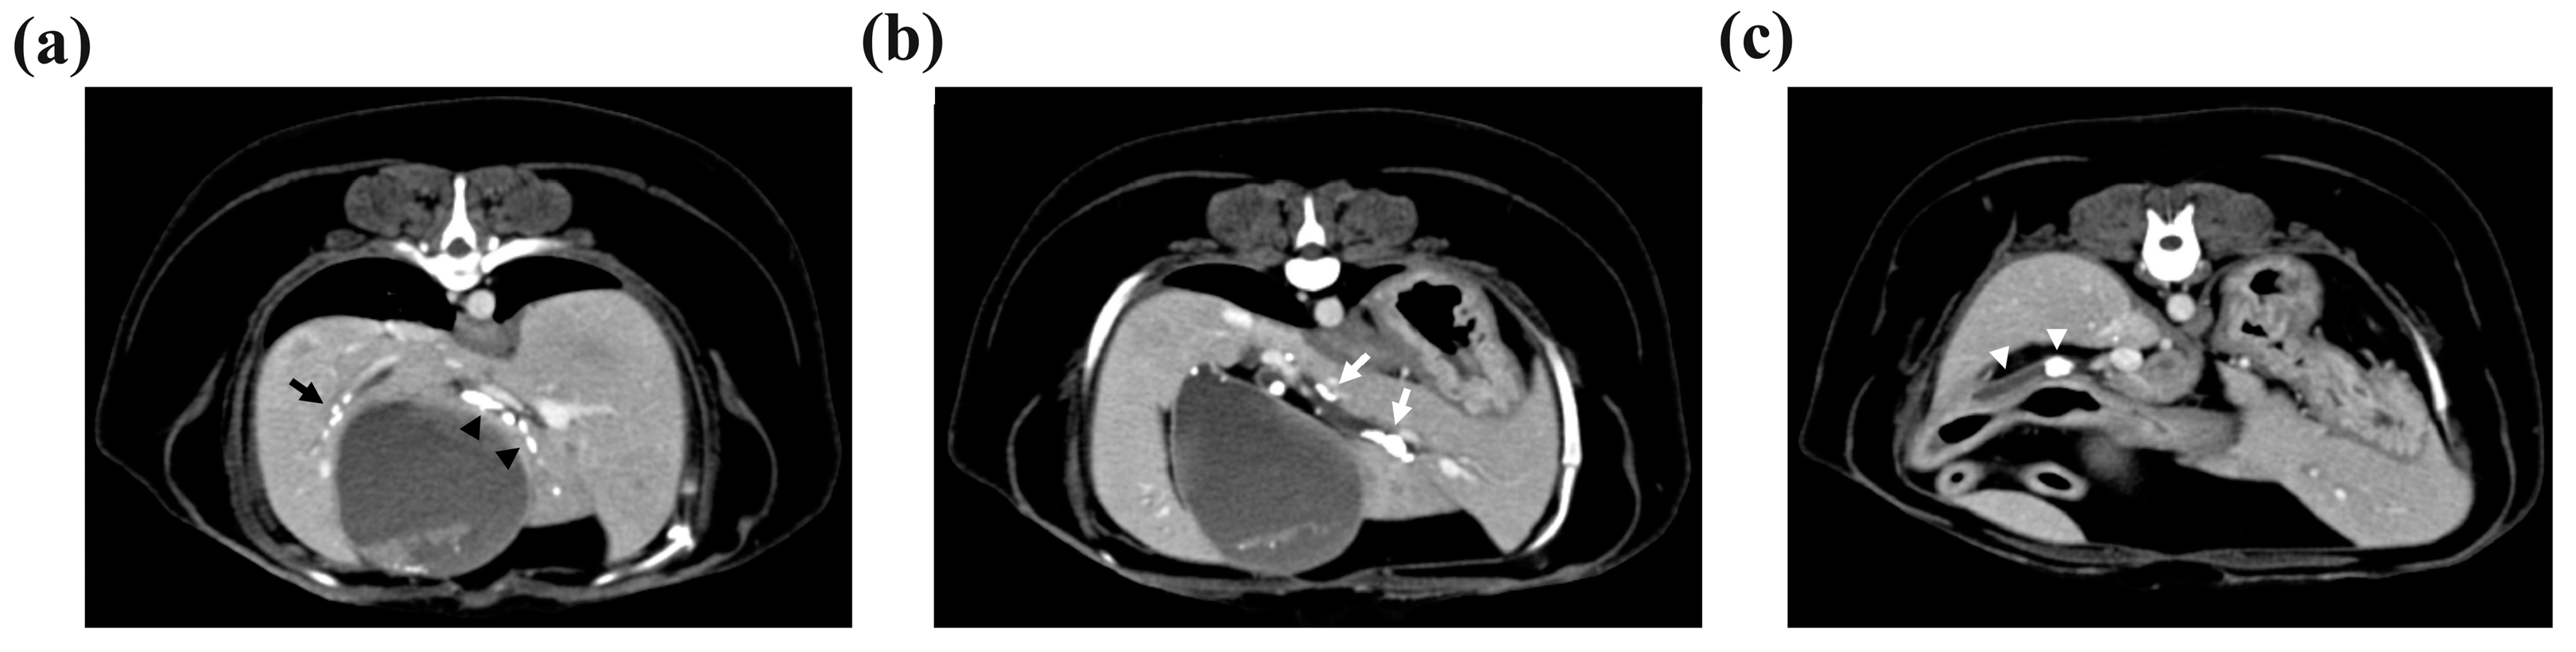

Computed tomography (CT) was performed to determine the size and location of the gallstones and whether there was obstruction or dilatation of the biliary system for surgical planning. The CT scan revealed cholelithiasis in the GB, the left, quadrate, and right liver lobes, and the CBD (Figure 2). Multiple intrahepatic gallstones were observed, and the hepatic duct in the left medial liver lobe was dilated with a diameter of 4 mm. The CBD was also dilated to 7 mm, and two gallstones were also identified.

Figure 2. Multiple cholelithiases identified on the computed tomography scan. (a) Cholelithiasis in the right liver lobe (black arrow). The diameter of the gallstone was <3 mm. There was no other dilatation of the intrahepatic duct. In the quadrate liver lobe, cholelithiasis was identified from the hilus to the peripheral intrahepatic bile duct (black arrowheads). Mild 3 mm dilatation of the intrahepatic duct was observed. (b) Cholelithiasis in the left medial liver lobe. The diameter of the largest gallstone was 7 mm, and the left hepatic duct was dilated to 4 mm (white arrows). (c) Two gallstones with 4.8 mm and 9.8 mm diameters were observed in the common bile duct, which was dilated to 7 mm (white arrowheads).